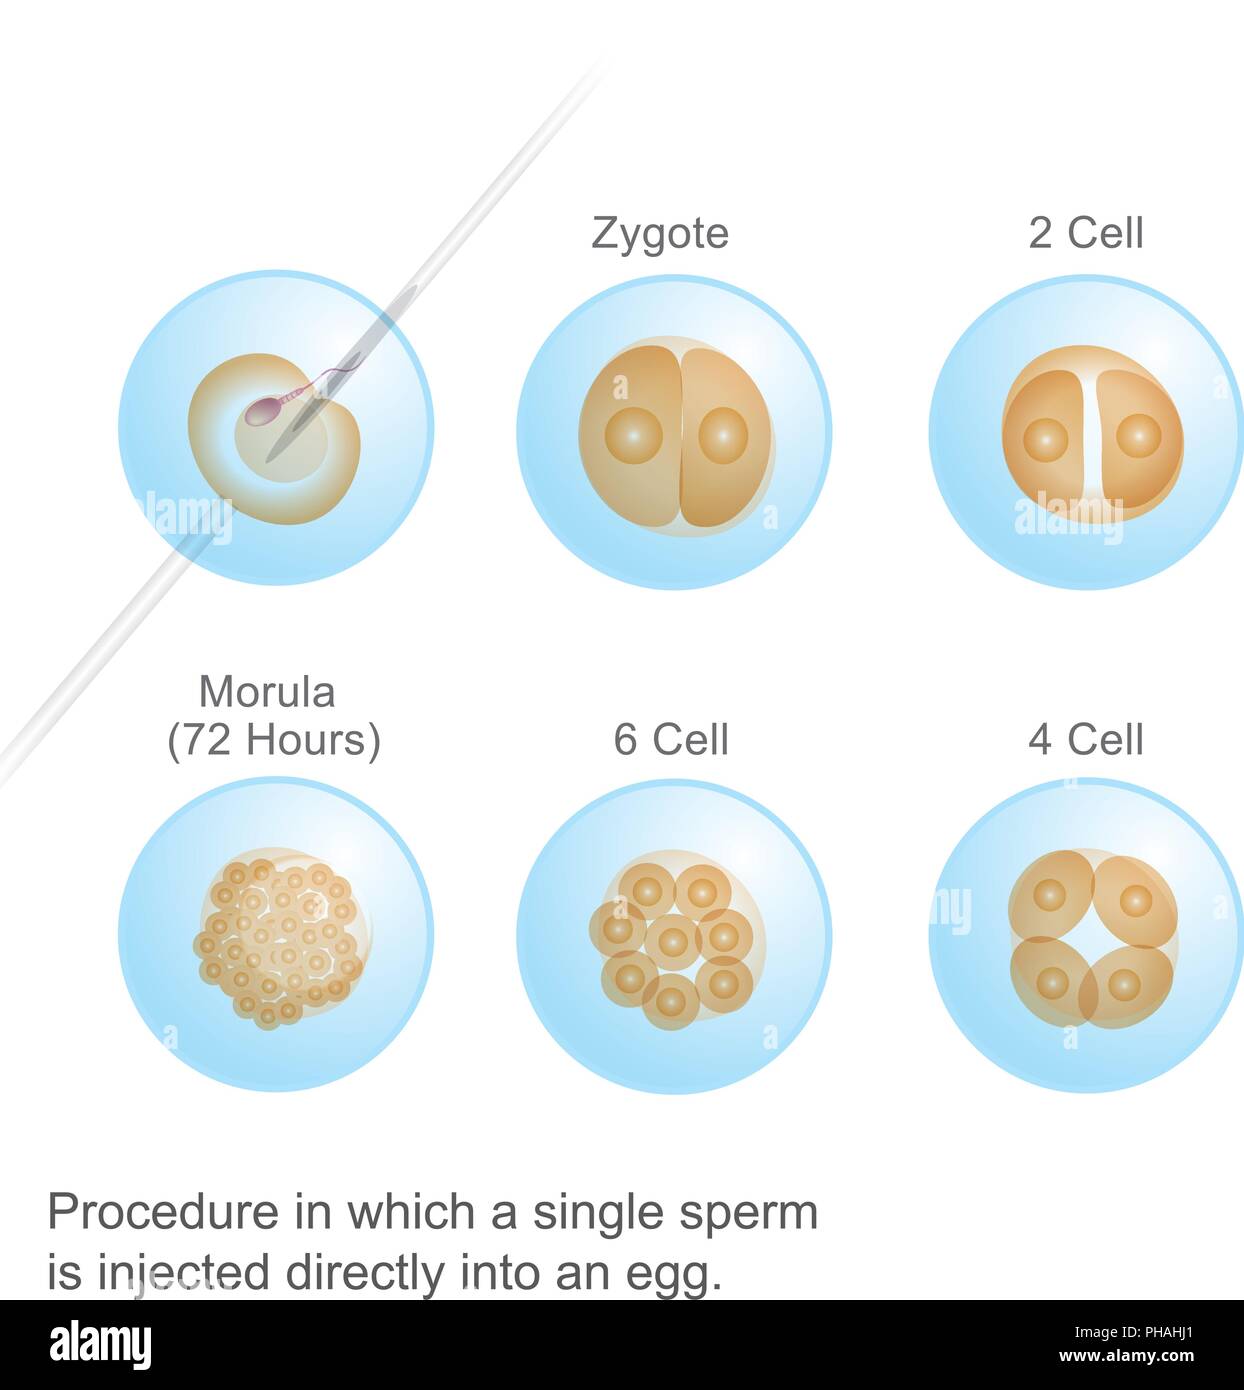

Un processo in cui un singolo spermatozoo. Immagine che mostra il corpo di Anatomia Umana. Illustrazione Vettorialehttps://www.alamy.it/image-license-details/?v=1https://www.alamy.it/un-processo-in-cui-un-singolo-spermatozoo-immagine-che-mostra-il-corpo-di-anatomia-umana-image217206921.html

Un processo in cui un singolo spermatozoo. Immagine che mostra il corpo di Anatomia Umana. Illustrazione Vettorialehttps://www.alamy.it/image-license-details/?v=1https://www.alamy.it/un-processo-in-cui-un-singolo-spermatozoo-immagine-che-mostra-il-corpo-di-anatomia-umana-image217206921.htmlRFPHAHJ1–Un processo in cui un singolo spermatozoo. Immagine che mostra il corpo di Anatomia Umana.